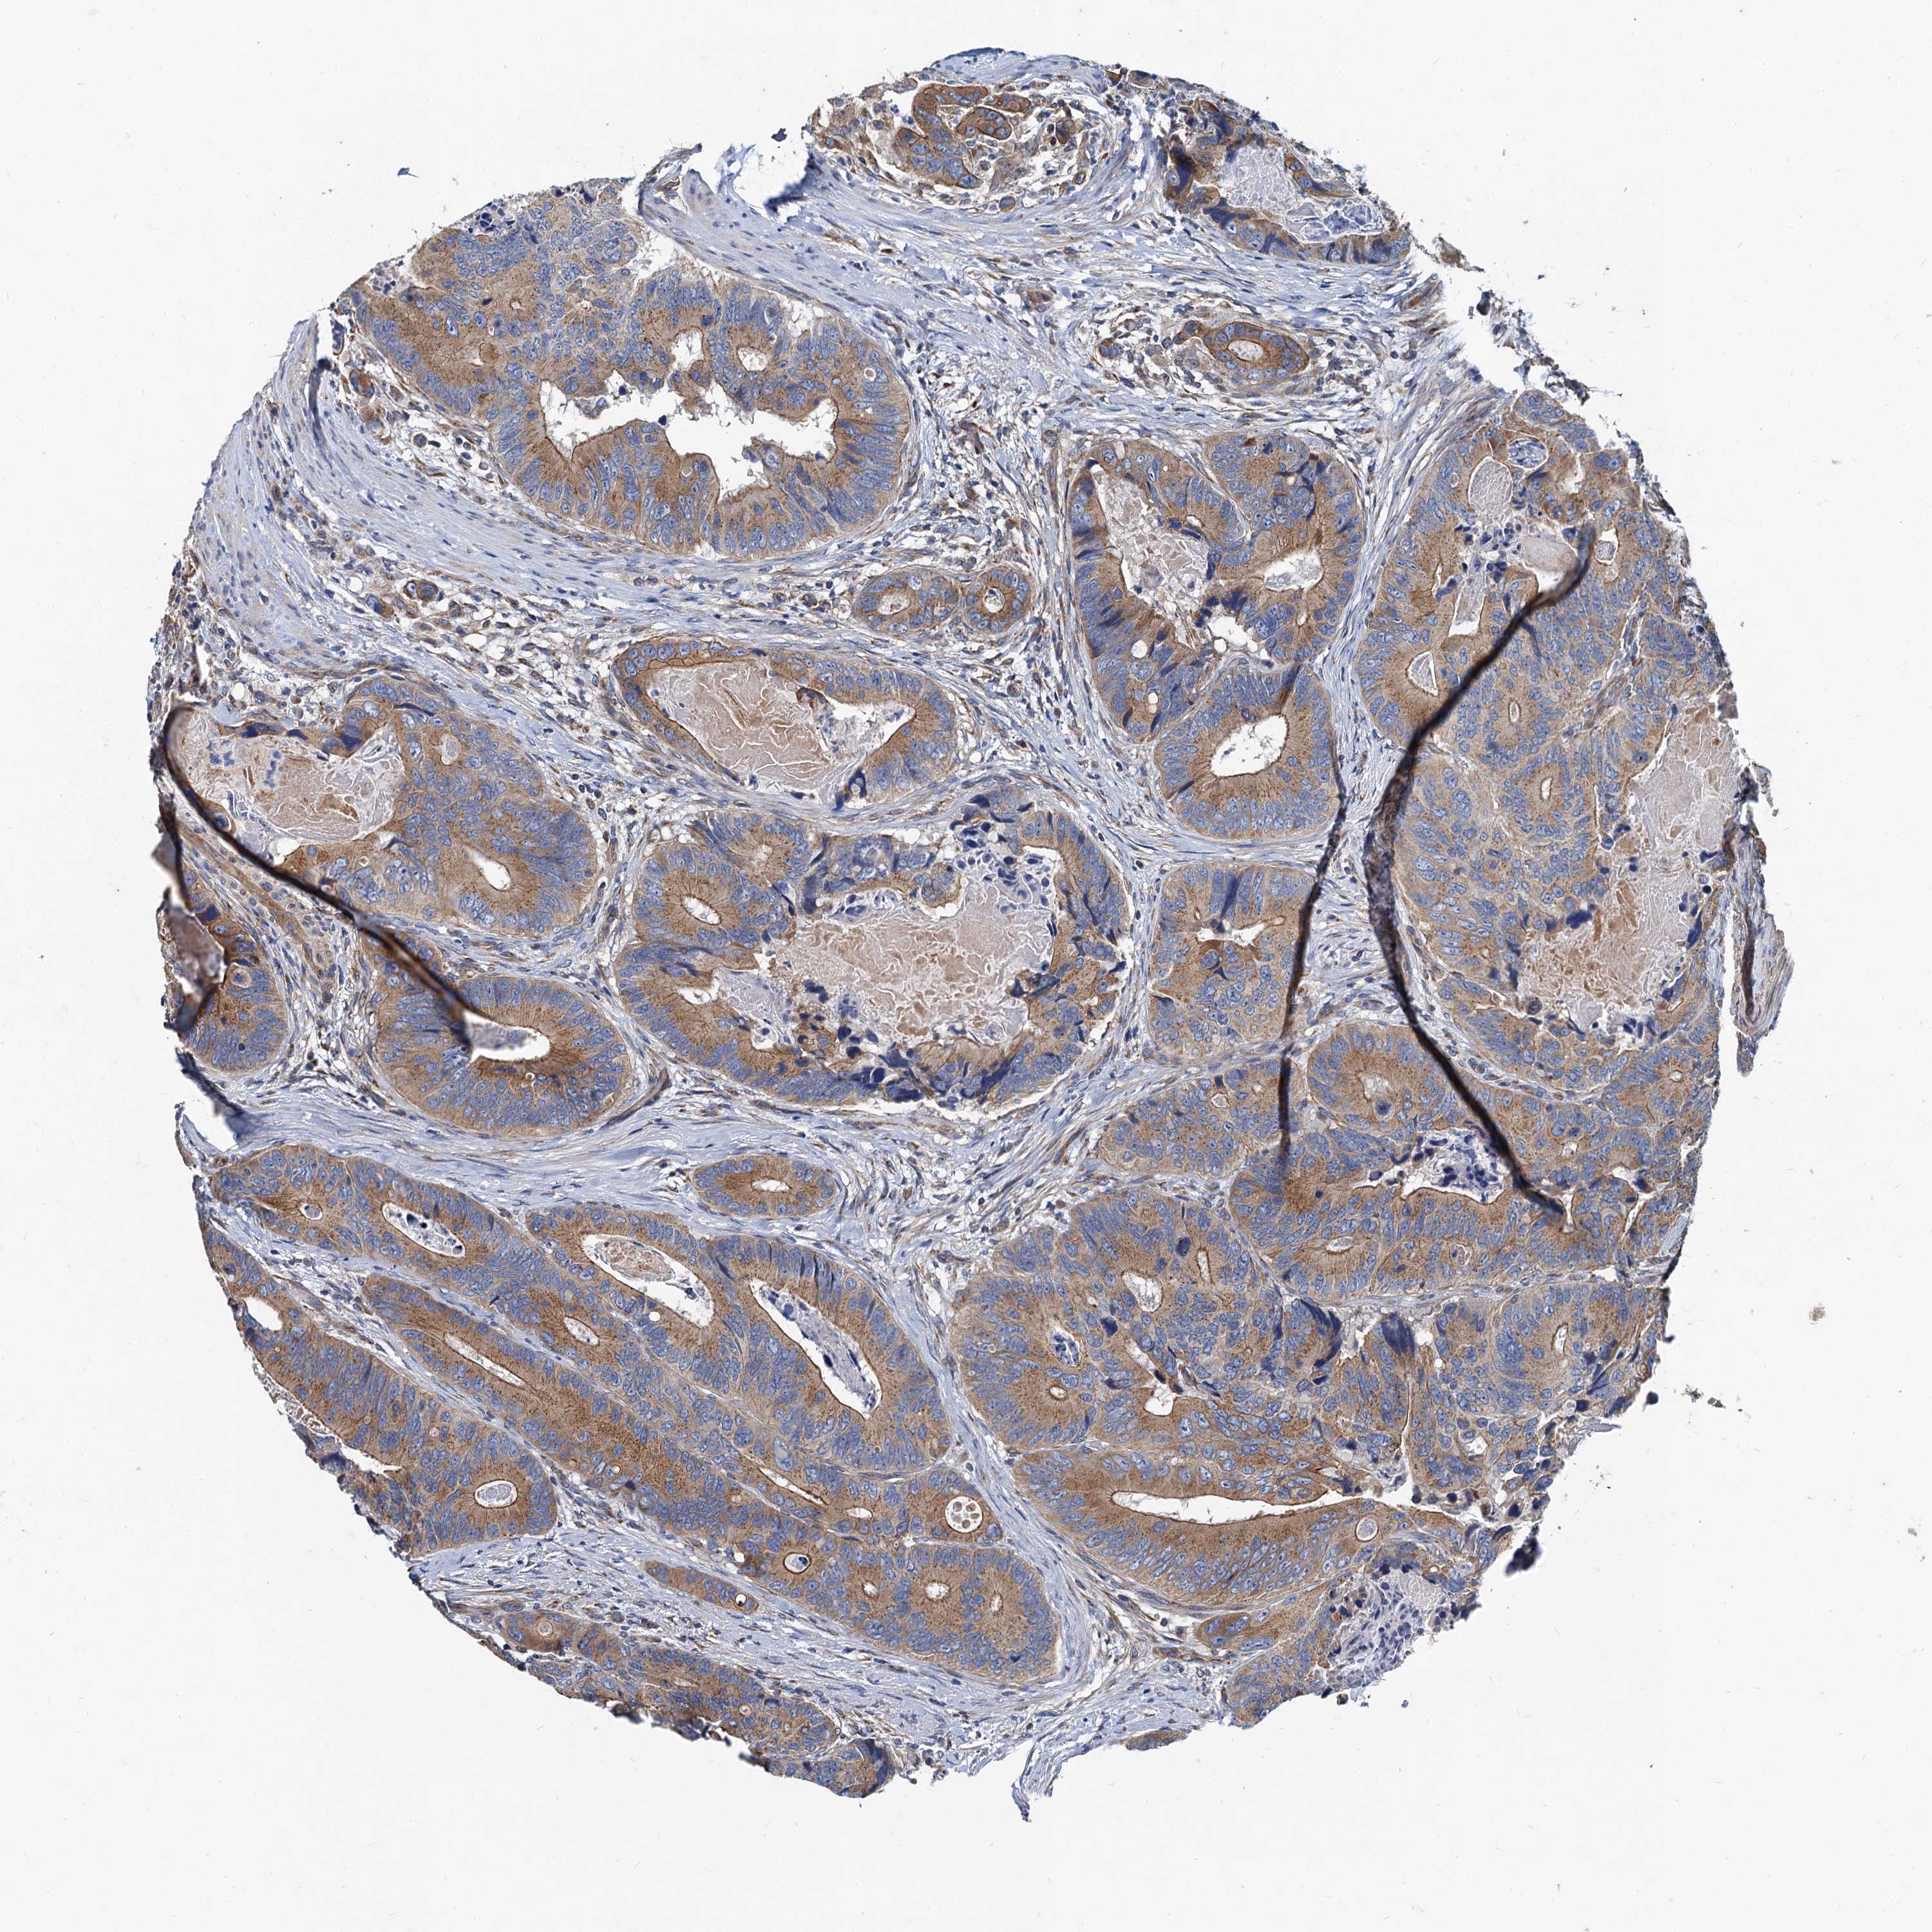

CANCER COLORECTAL CANCER Show tissue menu

COAD TCGA COAD VALIDATION READ TCGA READ VALIDATION PROTEIN COAD CPTAC PROTEIN EXPRESSION

ANTIBODIES

AND

VALIDATION